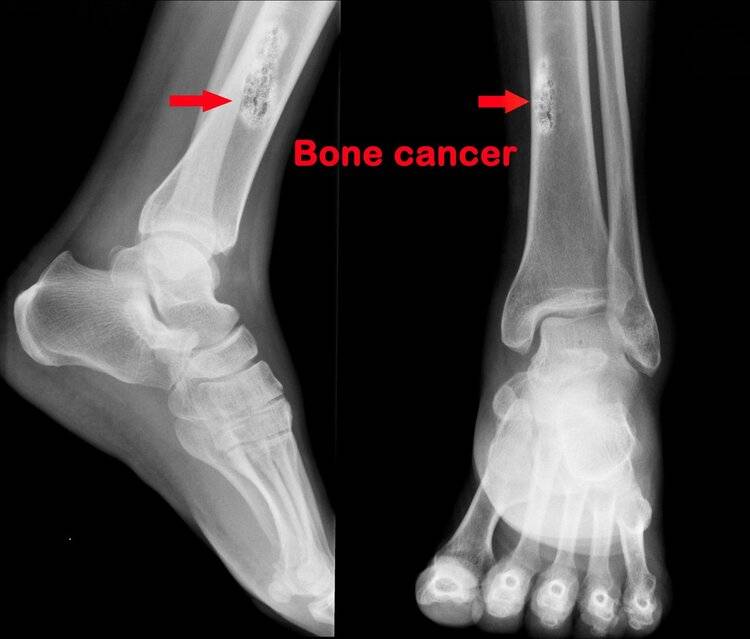

“没事的,爸爸只是得了鼻炎,很快就出院了。”阿斌(化名)强颜欢笑,只能这样安慰小女儿。 小女儿今年9岁,是他最大的牵挂。 指导专家:广西医科大学附属肿瘤医院 放疗科 主任医师 李龄 01 四十不惑,他被查出鼻咽癌晚期 42岁的阿斌家住广西宾阳县,和妻子育有一儿一女,虽然家庭条件比较一般,但日子也还过得去,一家人无话不说,没有代沟。 可就在去年,上天给跟阿斌开了个不小的玩笑。 去年7月初,阿斌在晨起刷牙时发现,脖子的左侧长了一个“鼓包”。一开始他以为只是淋巴结肿了,因为最近喉咙发炎比较严重。可吃了一星期的消炎药,肿块不但没好转,反而变大了一些,按压出现疼痛感。  保险起见,他决定去趟医院。 “肿物活检提示鼻咽未分化型非角化性癌,并考虑左侧颈部、左侧锁骨上窝淋巴结转移,建议立即治疗。”医生做完活检和增强CT检查后下了定论,阿斌被确诊鼻咽未分化癌IV B期(晚)。 非首诊医院02 经历放疗、化疗,却迎来多处复发转移 住院后,为尽快控制住病情,阿斌立即进行了第一个周期化疗,行奈达铂 130mg d1方案。首次化疗结束后,他又接受了6次放疗,周期为一个月。(PGTV6000CGY/30F GTV6000CGY/30F;6000CGY/30F;6000CGY/30F;5400CGY/27F;5400CGY/27F) 即便正处于壮年,阿斌也经不住放化疗的折磨,一个多月时间,阿斌的体重从69kg掉到58kg,恶心、头晕、怕冷等副作用一路随行,整日昏昏沉沉,可一躺下还是睡不着。 幸运的是,首次治疗后阿斌的肿块明显缩小,妻子的陪伴、女儿的鼓励,成为支撑他活下去的最大动力。 但就在首次化疗结束后一个月,阿义出现下腹部胀痛、左下肢麻痛,进一步筛查发现,他身上出现了多处转移,包括两肺多发转移瘤和肝尾叶、右后叶多发转移瘤。  从19年11月20年5月,医生为其实施7次化疗,前四次化疗方案为:多西他赛 120mg d1+奈达铂140mg d1,第五次化疗方案为吉西他滨 2g d1,8+顺铂40mg d1-3,第六次化疗方案为吉西他滨2g d1,8+顺铂40mg d1-3。 第六次化疗结束后,阿斌办理了出院手续。原来,经过几个月的治疗,他的“家底”已经被掏空,能借的、能贷的都想尽了办法,可他看不到这个“无底洞”究竟有多深。 2020年5月底,阿斌终于凑够了最后一次化疗的费用,回到医院行吉西他滨 2g d1治疗。治疗后,医院以“鼻咽癌放化疗后复发骨转移”将阿斌再次收治入院,  放化疗,多发转移,继续化疗,考虑骨转移。阿斌的情况不容乐观,目前仍在进一步治疗,希望他能挺过这一关。 鼻咽癌,我国南方高发癌,哪些人最容易得? 鼻咽癌,在我国南方地区最为常见,尤其是广东省,发病率约为30/10万,占全国鼻咽癌患者的60%,男性发病率是女性的两倍,而生存率却不太理想。据统计,鼻咽癌的整体5年生存率约为60%,但原位复发率达到10%~20%,而复发患者5年生存率仅10%~20%。 据研究,广东高发鼻咽癌的原因主要有3个。一是遗传因素,广东地区的居民鼻咽癌发病率高于其他地区,粤语地区的发病率高于闽南语地区或客家方言地区;二是饮食因素,其大米和水中的镍含量较高,也与常年食用腌鱼、腌菜等习惯有关;三是EB病毒感染,与EB病毒高危亚型的高发有关(BALF2_CCT亚型)。  可见,鼻咽癌整体形势比较严峻,所以大家要提高警惕,做好防患,尤其是鼻咽癌的高危人群。 ·有鼻咽癌家族史者; ·生活在鼻咽癌高发区、年龄30-59岁的当地居民(南方五省:广东、广西、湖南、福建、江西); ·出现原因不明的头痛、鼻塞、鼻涕带血、鼻衄、耳鸣、听力下降等症状,尤其是反反复复,经过常规治疗不愈的患者; ·长期吸烟、经常接触油烟和化学毒物的人群; ·有慢性鼻咽疾病史的人群; ·不明原因颈部触摸到无痛性的肿大淋巴结者。  这些人群除了定期进行相关筛查外,还要多留意身体是否有出现鼻咽癌可疑症状,以便于有问题可以及时就医。 鼻炎鼻咽癌,别再傻傻分不清 鼻咽癌早期症状不是很典型,很容易和鼻炎等病混淆,从而延误病情,查出时多已到中晚期,大大降低了疗效,大家一点要学会辨别。 鼻咽癌的症状: 出血 如果早晨起来,经常发现鼻涕中带血或吸鼻后痰中带血,要当心鼻咽癌。很多时候由于鼻涕带血量不多,很容易被忽略,而鼻炎虽然也会有出血现象,但基本是搽鼻涕时太用力引起的,短时间内可止血。 鼻塞 大部分时候都是单侧鼻塞,随病情发展,症状加重,可能出现双侧鼻塞。鼻炎也可引起鼻塞,但通常有2大特点不同于鼻咽癌:一是间歇性,白天劳作时鼻塞可减轻,夜间静坐时可加重;二是交替性,也就是侧着睡的时候,靠床的鼻腔易阻塞,上方的鼻腔通气良好。  颈部淋巴结肿大 肿大的淋巴结质地比较硬,活动度差,但没有什么不适感,有时候多个淋巴结可融合大一块形成巨大的肿块,看起来脖子一边大一边小。 耳鸣、听力下降 随肿瘤增长,堵塞到咽鼓管口时,可引起肿瘤所在一侧耳鸣、耳闷塞感及听力下降。 头痛、面麻、复视 而如果肿瘤向上生长,侵犯颅底骨头,影响三叉神经,可出现头顶部、枕部、颞部疼痛,面部麻木、复视及视物模糊等症状。 还有一点很重要,一般情况来说,鼻炎在规范治疗后,症状可明显得到改善,长期慢性鼻炎也无需担心会发展成鼻咽癌,但如果是鼻咽癌,症状则可能会持续,甚至会加重影响其他部位。  所以,一旦发现症状反复且久治不愈,最好及时去医院检查一下,以求安心,尤其是鼻咽癌的高危人群,建议每年检查。 鼻咽癌高危人群,建议每年检查 对于没有症状的高危人群,健康筛查可以参考以下策略: ①EB病毒相关抗体三联检,可作为初步筛查方案,该检查方法可适用于大规模人群。 ②如果当中某项检查持续阳性或者多项阳性,要高度警惕鼻咽癌,应将其列为高危人群,及时进行下一步检查。 进一步检查推荐鼻内窥镜,可直接窥视到鼻腔内的许多重要部位及鼻咽部的细微病变,如果发现异常增生物,还可以直接取样行病理活检,做最终的确诊。  提醒:即便没有发现明显的占位病变,还是要定期检测,同时,健康规律地生活,远离致癌因素。 一旦查出鼻咽癌,及时治疗是关键。 在过去,放疗或以放疗为主的综合治疗是鼻咽癌的主要治疗手段,由于主要接受放射的部位为头颈部,副作用比较明显。 近几年,质子疗法的应用很好地弥补了化疗的不足,在提升疗效的同时有效减少了不良反应及二次肿瘤的发生,晚期5年生存率可达74%。质子疗法的价格比较昂贵,普通家庭难以接受,不过大家也别灰心,如今国内质子治疗技术发展迅猛,多家质子中心落地,相信不久,会有更“亲民”的价格。 6 O: P3 o( i% _